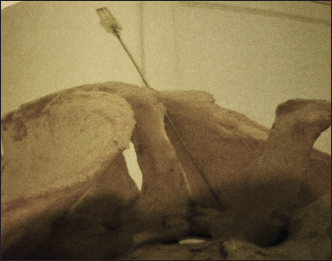

2. Sacroiliac joint (SIJ) injection

For accurate accessibility of SIJ, 3 transverse sections at the sacral region of the back (as anatomical cadavers specimens intended for dissection) and an osseous construction pf sacro-pelvic specimen were used to test the feasibility of injection in a predetermined anatomical location (Fig. 4).

Forty horses with suggestive SIJ complaints were used to evaluate the potential of diagnostic SIJ analgesia based on previous anatomical studies. Following restraining the horse in stanchion local aseptic preparation of the sacral region, A 13 cm, a 21-gauge needle was inserted axially to the cranial aspect of the ipsilateral sacral tuber according to the rider’s complaint side of the horse (left or right). The needle was directed obliquely and caudally at 30º to the vertical of the same side toward the SIJ. The needle was then advanced until contact was made with the bony floor formed by the sacral spine and medial iliac wall of the SIJ. Twenty milliliters of MepivacaineR, 2% were perfused in the vicinity while the needle was partially withdrawn to walk the horse for 15 minutes after injection before being assessed and ridden.